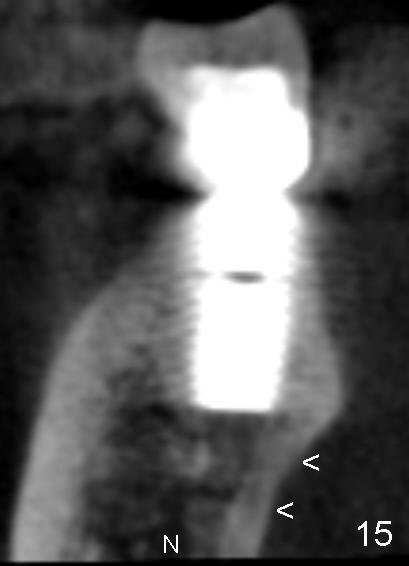

In addition, it is important to control the depth of the osteotomy. For freshly healed socket and immediately post-extraction socket, it should be safe to place a 11 mm long bone-level (Fig.15,16) or 14 mm gingival level (Fig.13,18) implant or less. For the same length, it appears safer to use a tapered implant (Fig.9,13,18) than cylindrical one (Fig.15,16).